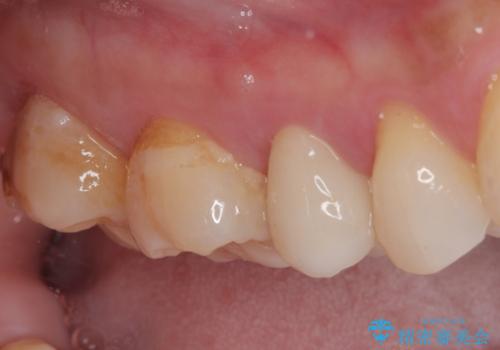

- むし歯と銀歯を気にして来院された患者様です。

銀歯の歯は既に根管治療がされており、根尖部に病変が認められないため、根管治療を行うことなくオールセラミッククラウンにて補綴治療を行うこととしました。

むし歯の症状のある歯は、ややしみることがある程度でしたが、レントゲン写真では非常にむし歯が大きく、神経組織に迫っている状態でした。

術前診査では神経を全て取る可能性は低いと予想されましたが、一部切除する可能性があることを伝えた上で治療を行うこととしました。